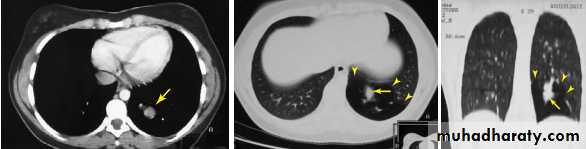

Fluoroscopy ( dynamic ) Analogue or digital : Used in contrast studies and interventional procedures .CT scan (Computed tomography scan )

Computed tomography or CT is an imaging modality that produces cross-sectional images representing the X-ray attenuation properties of

the body.

A- CAT (computed axial tomorgaphy ) scan

Single-slice CT , Circular CT

The most straight forward way to image an entire volume is to scan a number of consecutive slices by circular tube–detector rotations alternated with small table shifts.

B- Spiral CT (Helical CT)

A technique that is widely used nowadays is helical CT.The X-ray tube rotates continuously around the

patient, just as in 2D CT. At the same time, the patient

is slowly translated through the gantry.

Multidetector spiral CT scan ( 16 slice , 32 slice , 64 ,128 and 256 slice) .

In modern CT scanners, the detector array consists of multiple detector rows, in order to measure several slices per rotation of the X-ray tube.Biologic effects and safety